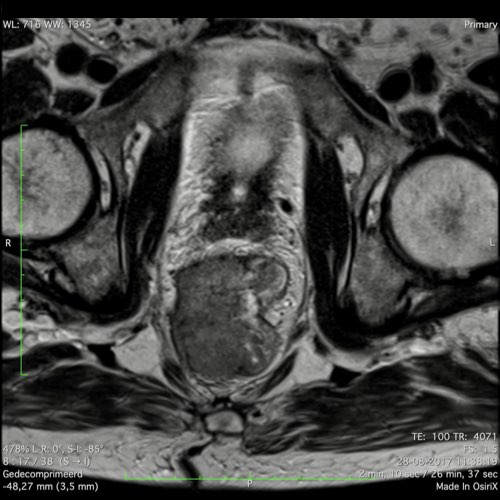

Hình ảnh

Các hình ảnh được cung cấp cho thấy ung thư biểu mô tế bào nhẫn với tình trạng dày lan tỏa thành trực tràng, hình ảnh bia bắn điển hình, và sự xâm lấn mỡ mạc treo trực tràng.